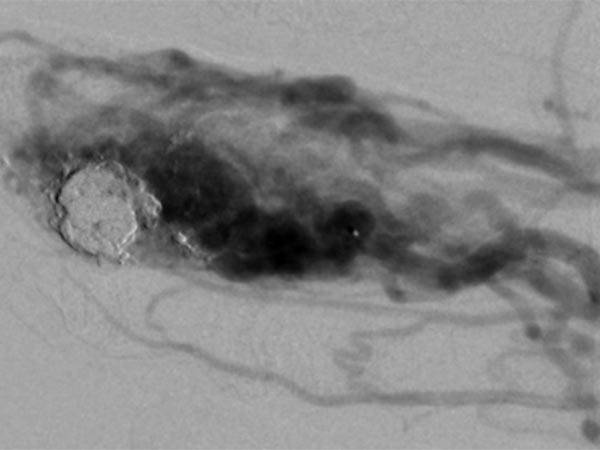

Nach bereits erfolgter transarterieller Teilembolisation der AVM am Finger vor 2 Jahren zeigt sich ein Rezidiv der AVM. Bei der Embolisation wurde nur ein Teil der AVM verschlossen, dies erhöht die Gefahr eines Rezidivs. Der alte Cast der vorherigen Embolisation ist zentral als Kontrastmittelaussparung zu erkennen.

Das Rezidiv der AVM hier in der vergrößerten Zielaufnahme des D III während der Angiographie mit deutlicher Vergrößerung im Vergleich zu den alten Angiographien (nicht abgebildet). Die DSA-Aufnahmen nach transarterieller antegrader Punktion der Arteria brachialis zeigen eine hypervaskularisierte AVM von Fingermittel und -endglied.